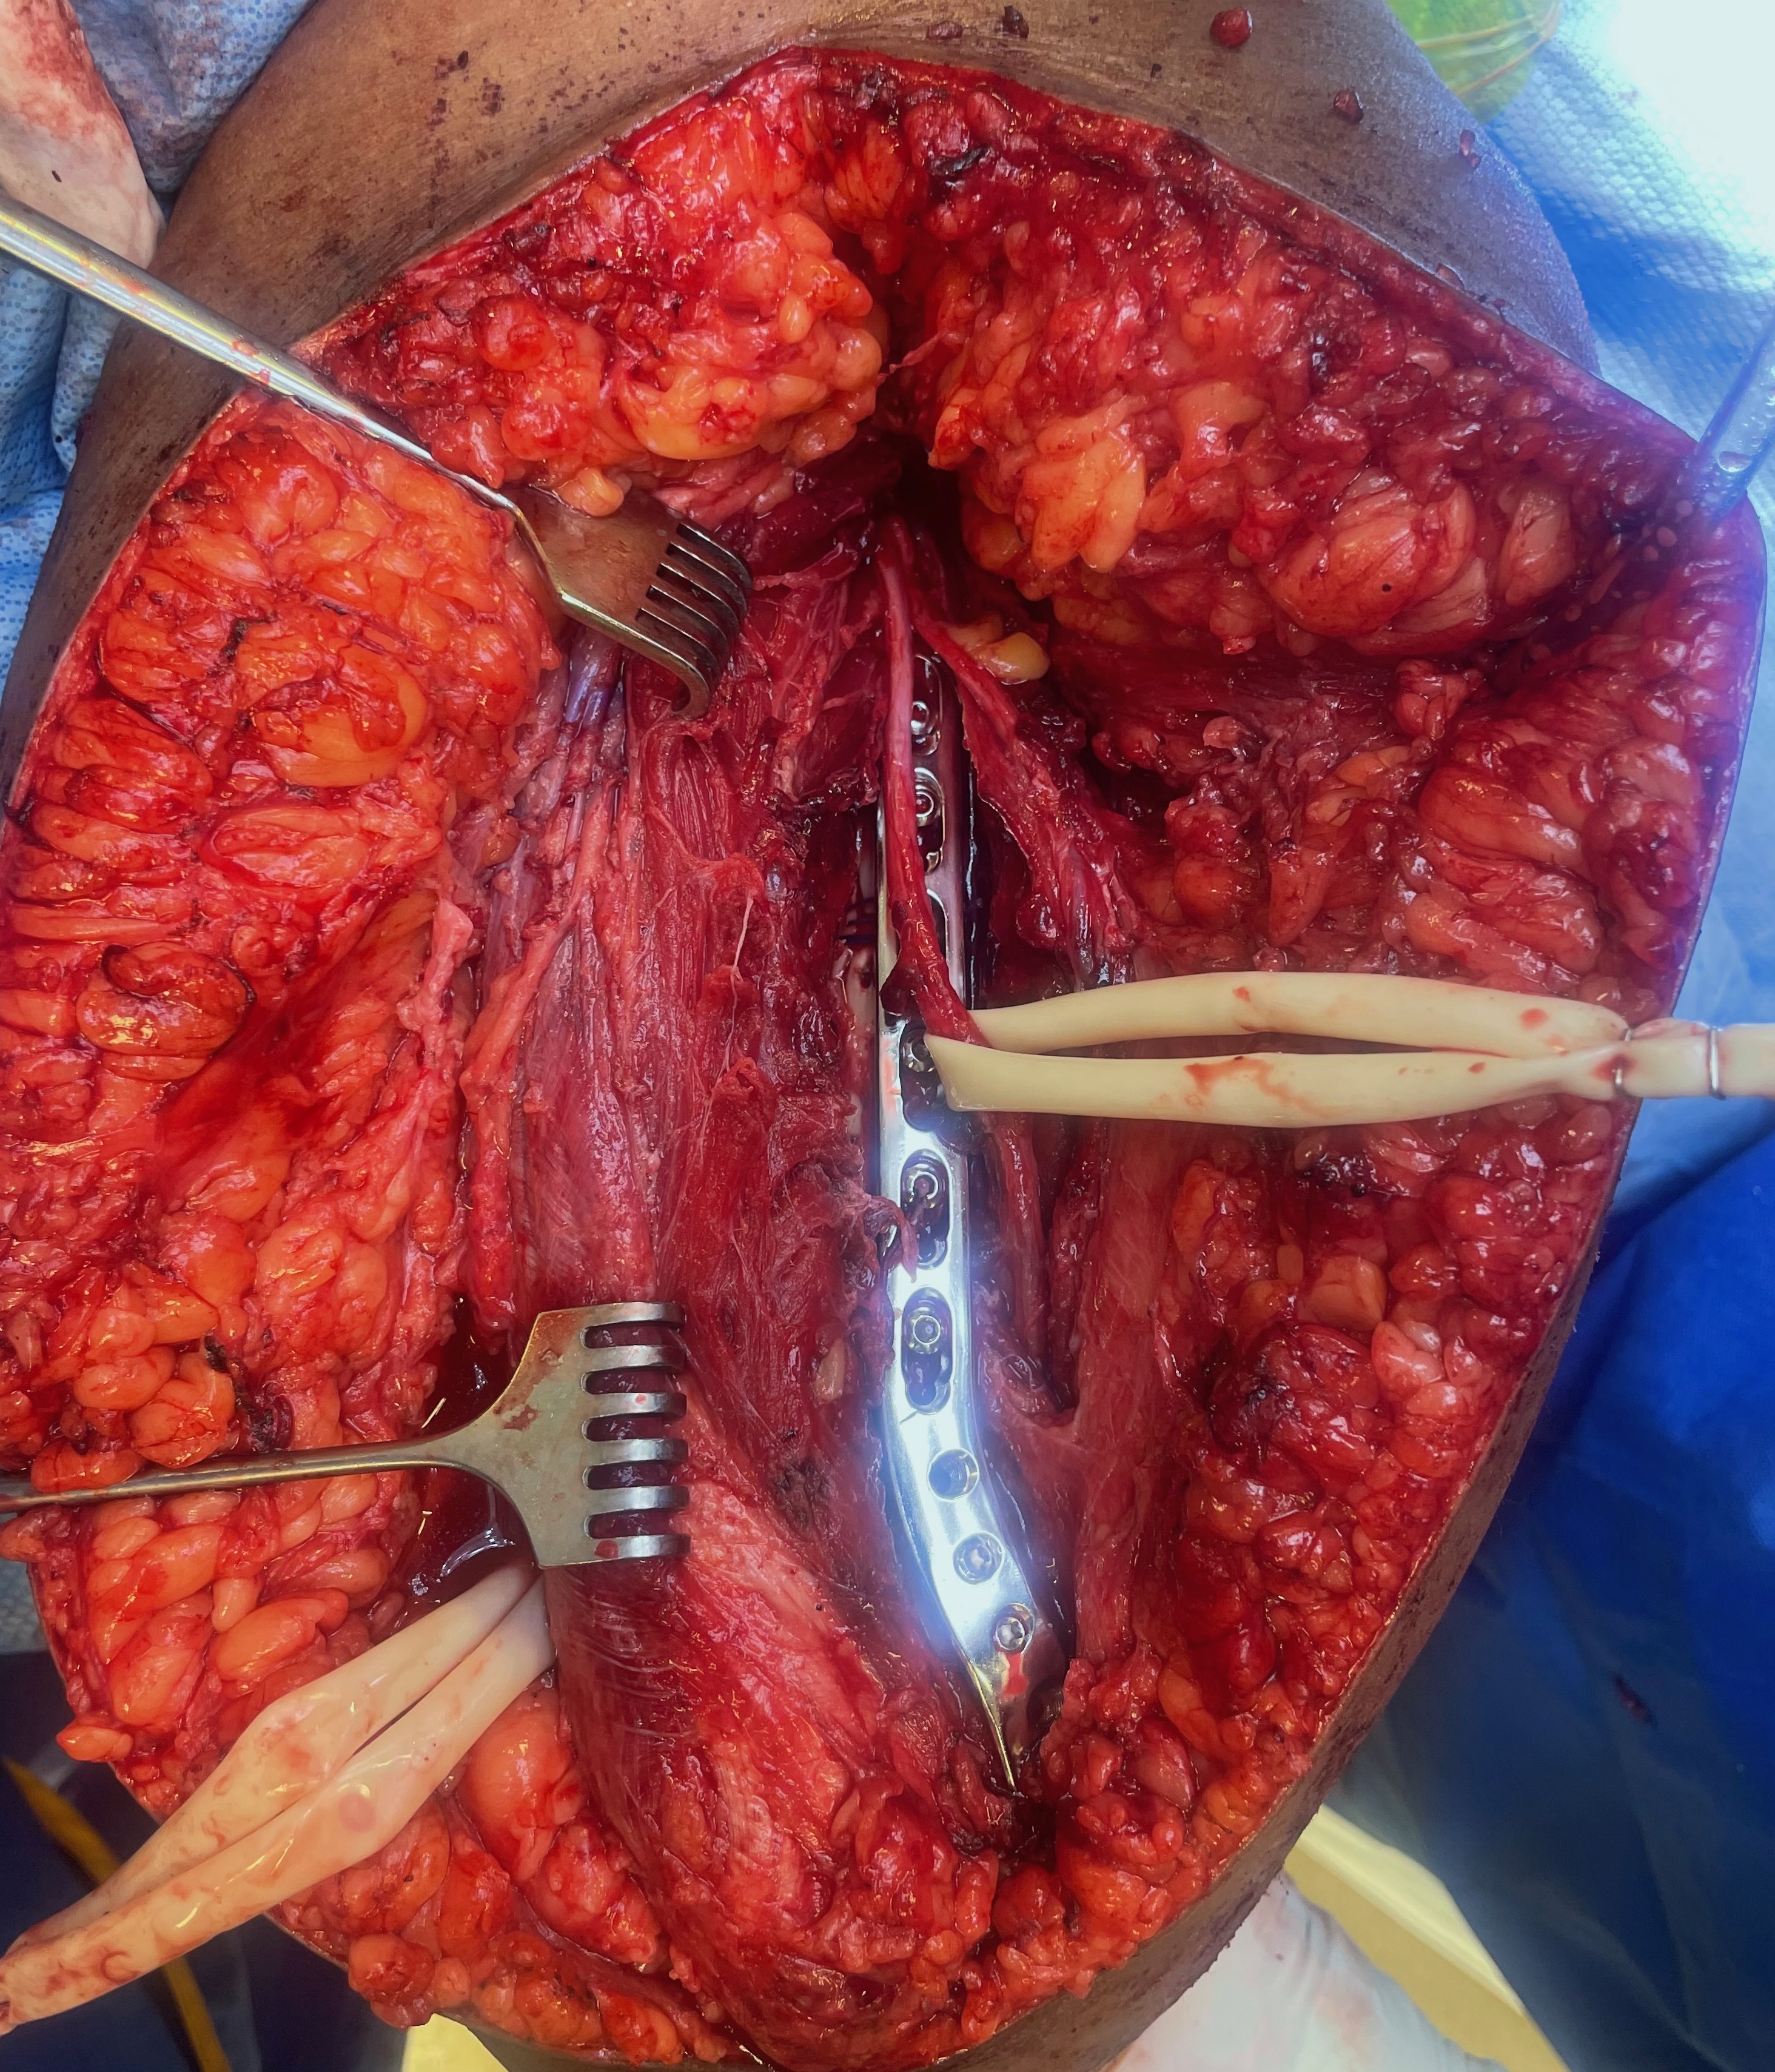

A. Mobilise the lateral triceps medially from lateral intermuscular septum

B. Identify and protect the radial nerve lateral to triceps

- pierces the lateral intermuscular septum 10 from articular surface elbow

- enters spiral groove 14 cm above lateral epicondyle

- posterior antebrachial cutaneous nerve arises here from radial nerve

- may have to elevate the radial nerve and pass the plate under

- apply precontoured long posterolateral distal humerus plates

Release and protect radial nerve, and place plate under nerve

Posterolateral plate

C. Can use proximal window between long and lateral heads

- slide plate under radial nerve

- fix with screws proximal and distal